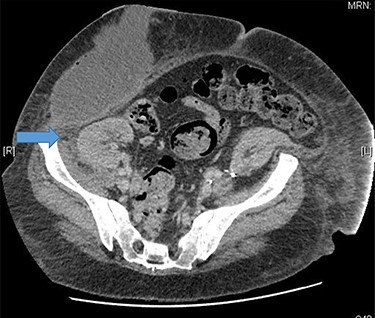

A 48-year-old lady was admitted from the outpatient surgical clinic with a painful lump in the right iliac fossa for a duration of 4 weeks. The patient had undergone kidney autotransplantation long time ago and she had a rooftop incision over the overlying kidneys. Patient’s initial diagnostic impression was a query painful obstructed incisional hernia as a result of the previous renal surgery to denervate the nerves and re-implant the kidneys to a different location within the abdominal cavity. In order to confirm the diagnosis, a computed tomography (CT)-abdomen and pelvis with IV contrast was organized. The scan showed a large retroperitoneal loculated collection with tracking of fluid into the anterior abdominal wall, where there were tiny gas pockets close to the anterior margin (Figs 1 and 2). The patient was transfused with three units of packed red cells, given the impression of a chronic hematoma as per the CT scan. Our patient had undergone bilateral autotransplanted kidneys in the iliac fossa region.

Large right retroperitoneal loculated fluid collection superior to the right pelvic kidney with no internal gaseous contents.